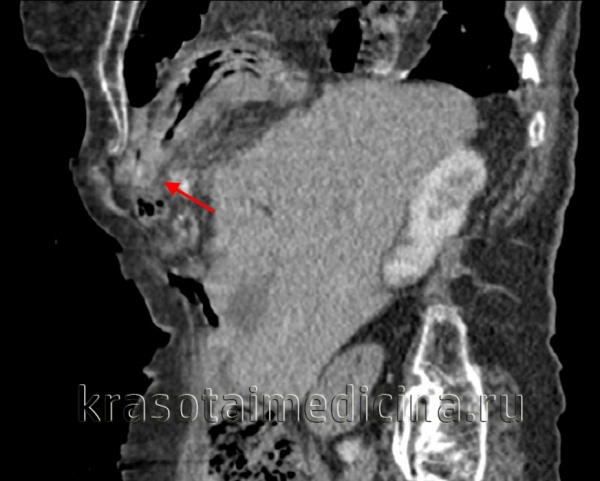

• Радиационная диагностика. Выполнены рентгенография и КТ грудной полости, КТ брюшной полости. Разрыв на рентгенограмме можно обнаружить только при выпадении органов пищеварения в области грудной клетки. Для выяснения местоположения травматического дефекта брюшной перегородки проводится дифференциальная диагностика травм и расслабления тела, проводится контрастная рентгенография желудка или ирригография. В левой половине грудной клетки видны петли желудка или кишечника, определяется смещение пищевода.

КТ молочной железы. Травматическое событие кишечника, сальника в грудной полости.